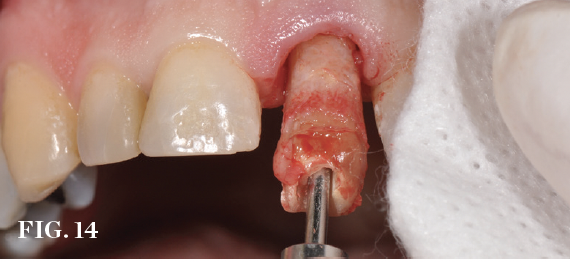

Minimally Traumatic Extraction

A range of extraction devices may be required, but it is essential to minimize the occurrence of surgically mediated bone loss to optimize the success of immediate implant placement (Figure 14).

(14.) Conservative extraction methods such as the use of a vertical extraction device

are important to minimize the occurrence of surgically mediated bone loss and optimize the success of immediate implant placement.

Figure 14